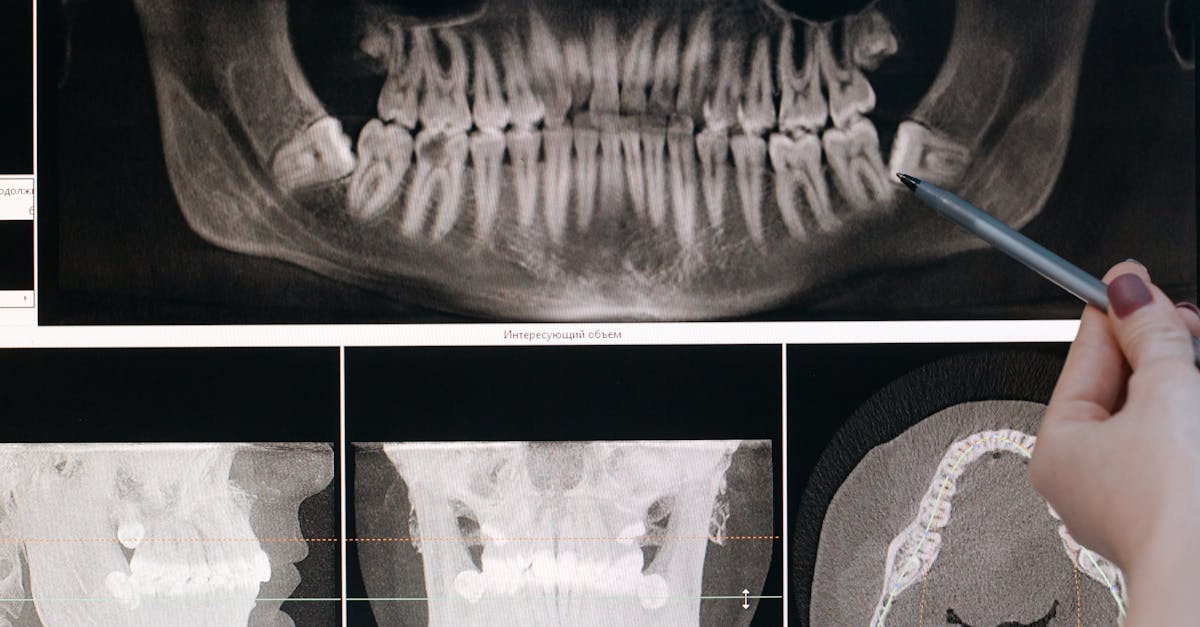

The degree of bone resorption can only be determined with a thorough dental evaluation and imaging. At Blanc Dental Center, we use advanced 3D X-rays (CBCT scans) and digital scanning to get a precise picture of your jawbone health, making it possible to determine the best course of action—even after many years without teeth.

• Plan for comprehensive diagnostics: Advanced imaging (CBCT 3D scans, digital impressions) ensures accurate treatment planning, which is vital to predictability and success.

• Advanced technology: Digital 3D X-rays, intraoral scanning, and computer-guided implant placement for precise, safe outcomes.